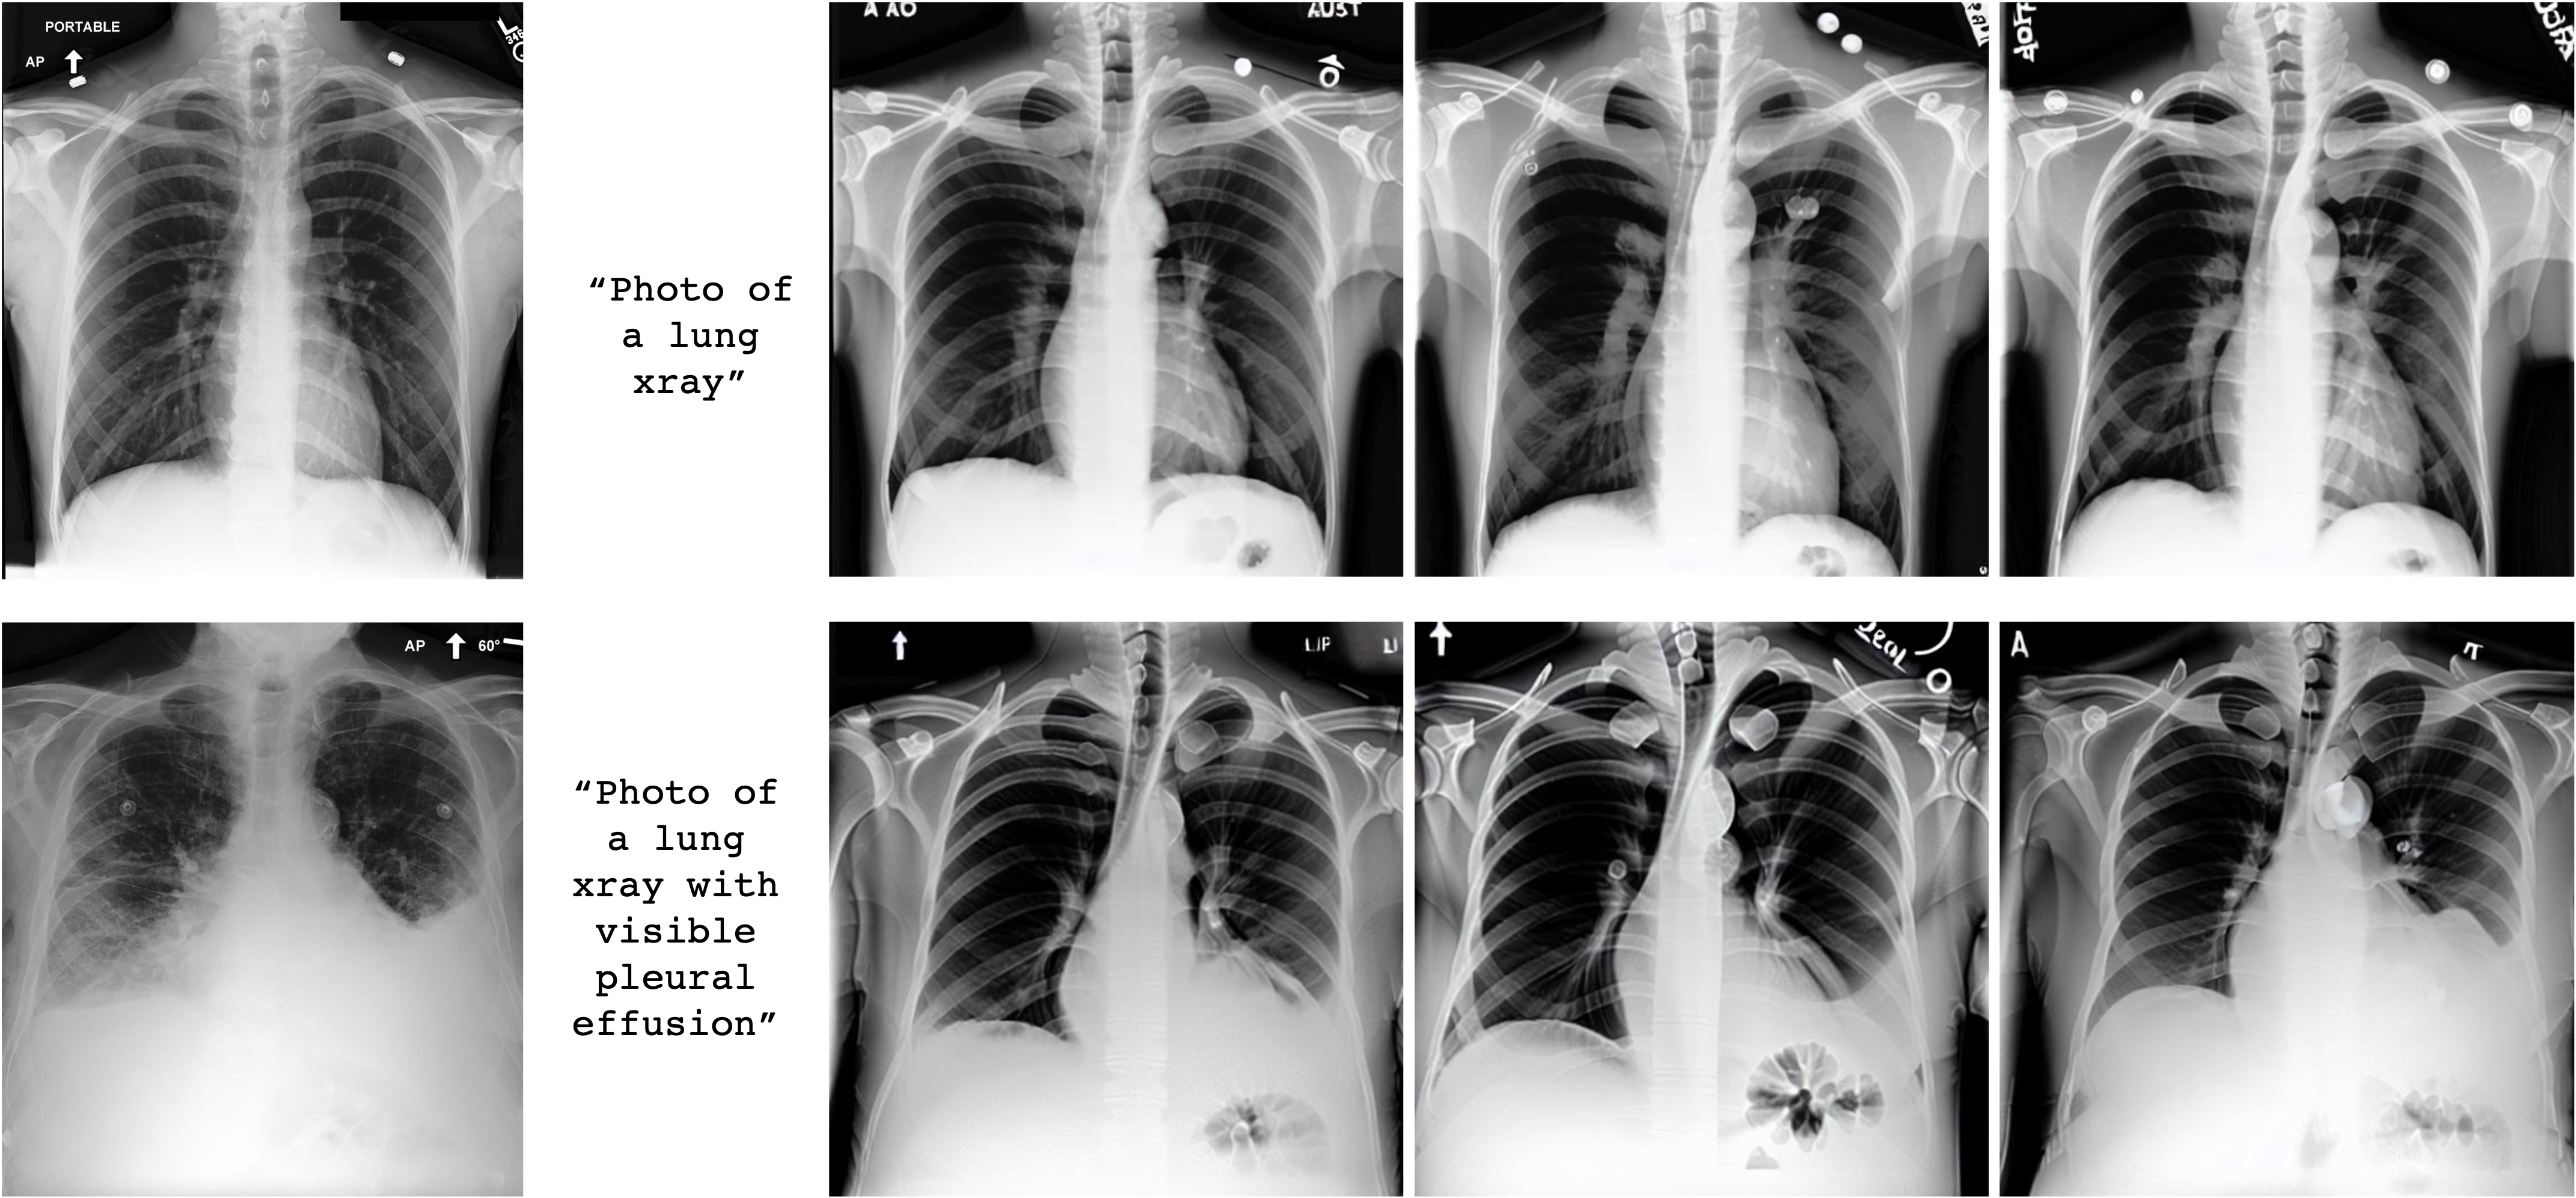

Refer to caption

Figure 1: Generated images by both the original Stable Diffusion model and our fine-tuned model on radiology images. The prompts are designed to compare a standard radiology image with no particular findings, and the insertion of the frequently encountered finding "pleural effusion" (red arrow).

3.4 Radiology Image Generation

We tested the various generative models, after potential fine-tuning by one of the scenarios described in Section 2, with two simple prompts: "A photo of a lung xray" and "A photo of a lung xray with a visible pleural effusion". Based only on this text-conditioning, the models generated synthetic images. We used the Fréchet inception distance as introduced in Section 2.3 to measure the quality of the generated images. The results are compiled in Table 4, along an empirical sample of images as produced by each method in Figure 4.

For the most simple prompt "A photo of a lung xray", the baseline model, the Stable Diffusion model as released by Rombach et al. (2022), generates black-and-white thoracic images, visible on Figure 4, with associated FID-score of 0.097. Fine-tuning the stable diffusion model using the textual projection approach leads to a degradation of the generated images, with FID-scores that at least double for both the token-level and the document-level projections. Textual- inversion-based fine-tuning do not degrade performance much but do not allow for an improvement of the FID-score as well. Only with the method that consists in fine-tuning the U-net do we observe enhanced generated images, lowering the FID-score down to 0.034. For more complex prompts such as "A photo of a lung xray with a visible pleural effusion", the stable diffusion baseline shows even more limitations, with larger FID-score 0.151, being outperformed by both textual inversion and U-Net fine-tuning.